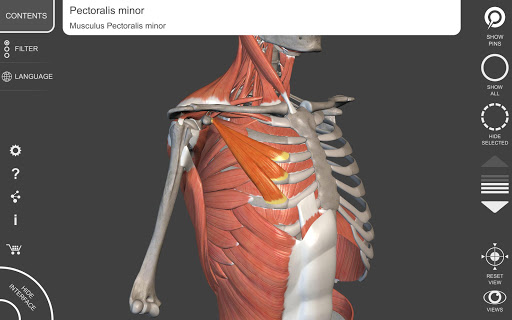

"Anatomía - Atlas 3D" permite estudiar la anatomía humana de forma fácil e interactiva.

A través de una interfaz sencilla e intuitiva es posible observar cada estructura anatómica desde cualquier ángulo.

Los modelos anatómicos 3D son especialmente detallados y con texturas de hasta una resolución de 4k.

La subdivisión por regiones y las vistas predefinidas facilitan la observación y el estudio de partes individuales o grupos de sistemas y las relaciones entre los diferentes órganos.

MODELOS ANATÓMICOS 3D

• Sistema musculoesquelético

nervioso • Sistema respiratorio • Sistema digestivo • Sistema urogenital (masculino y femenino) • Sistema endocrino • Sistema linfático • Sistema ocular y auditivo CARACTERÍSTICAS • Interfaz sencilla e intuitiva • Rotar y hacer zoom en cada modelo en el espacio 3D • Opción para ocultar o aislar uno o varios modelos seleccionados • Filtro para ocultar o mostrar cada sistema • Función de búsqueda para encontrar fácilmente cada parte anatómica • Función de marcador para guardar vistas personalizadas • Rotación inteligente que mueve el centro de rotación automáticamente • Función de transparencia • Visualización de músculos a través de niveles de capas desde las superficiales hasta las más profundas • Al seleccionar un modelo o un pin, aparece el término anatómico relacionado • Descripción de los músculos: origen, inserción, inervación y acción • Mostrar/ocultar interfaz de usuario (muy útil con pantallas pequeñas) MULTILINGÜE • Los términos anatómicos y la interfaz de usuario están disponibles en 11 idiomas: latín, inglés, francés, alemán, italiano, portugués, turco, ruso, español, Chino, japonés y coreano • Los términos anatómicos se pueden mostrar en dos idiomas simultáneamente REQUISITOS DEL SISTEMA • Android 8.0 o posterior, dispositivos con al menos 3 GB de RAM Reversi